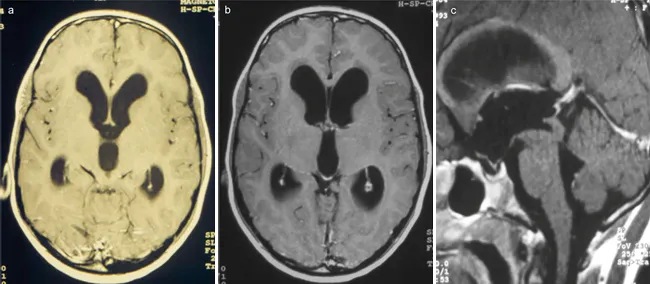

初始磁共振成像检查显示为三脑室梗阻性脑积水,导水管周围肿瘤压迫导致导水管管腔狭窄(图1)。

图1:术前磁共振图像显示,因病变压迫导水管,导致三脑室梗阻性脑积水,疑为低级别肿瘤。